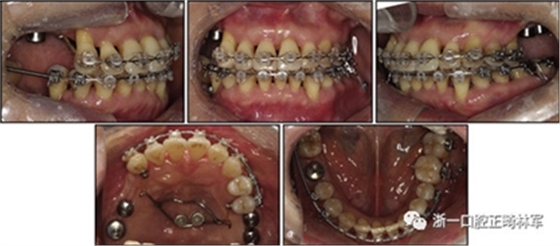

口腔內(nèi)由于牙周炎,她的上頜右側(cè)第一和第二前磨牙,上頜右側(cè)第一和第二磨牙,上頜左側(cè)第一和第二磨牙以及下頜右側(cè)第一磨牙缺失。牙周探查顯示在磨牙區(qū)域和下頜骨左側(cè)側(cè)切牙區(qū)有深的牙周袋,還存在出血(表I)。上頜骨和下頜骨前牙擁擠,左側(cè)側(cè)切牙存在反合,下頜左側(cè)側(cè)切牙發(fā)過度萌出。覆蓋是5毫米,上頜切牙是唇傾的。在上頜弓中,尖牙和前磨牙是近中傾斜,右側(cè)尖牙過度萌出。而且,下頜右側(cè)第二磨牙向近中傾斜。尖牙處于I類關(guān)系,但無法評估磨牙關(guān)系(圖1和2)。

圖2. 治療前牙齒石膏模型

拔除下頜左側(cè)側(cè)切牙,除了4顆前牙外,下頜和上頜牙齒通過0.022英寸的Clippy-C裝置(日本東京的Tomy)粘接聯(lián)合。磨牙管粘結(jié)在下頜磨牙上。排齊過程從0.014英寸的鎳鈦弓絲開始,然后是0.016英寸的鎳鈦弓絲。

為了美觀,在拔除的下頜左側(cè)側(cè)切牙間隙中放入一個修復(fù)體。為了防止牙齒的圓形轉(zhuǎn)動,4根上頜前牙被繞過,使牙齒能在尖牙被推向遠(yuǎn)中后排齊。將兩個TADs(Orlus,Ortholution,Seoul,Korea)放置在腭板,并且有鉤子附著。將一小段0.016英寸的不銹鋼弓絲放置在上頜左側(cè)尖牙和前磨牙上,并且通過附著在腭板上的鉤子將上頜尖牙和左側(cè)前磨牙推向遠(yuǎn)中。

對于近中傾斜和過度萌出的上頜右側(cè)尖牙,需要控制牙齒向遠(yuǎn)中傾斜和向下推入。用兩個鉤子在兩側(cè)施加不同方向的力,以期望右側(cè)尖牙的推入(圖7)。在上頜尖牙遠(yuǎn)中移動后,用一根0.014英寸的鎳鈦弓絲將4顆上頜前牙排齊。放置逐漸變硬的弓絲,直到上下兩個牙弓都放置0.017*0.025英寸的不銹鋼弓絲。

然后關(guān)閉下頜前牙區(qū)間隙,用完全相同的力學(xué)原理將上頜全牙列向遠(yuǎn)中移動,以獲得適當(dāng)?shù)母埠虾透采w。此外,還有一個0.017*0.025英寸β-鈦絲的直立彈簧應(yīng)用于下頜右側(cè)第二磨牙。當(dāng)直立彈簧接合到主弓絲上時,引起前磨牙的推入,第二磨牙的推出,前磨牙的頰側(cè)傾斜以及第二磨牙的舌側(cè)傾斜,以矯正牙弓形態(tài)(圖8)。

由于患者有多個缺失的后牙,因此考慮到具有垂直方向的喪失。然而,她在拔除后牙后立即去正畸科就診。她封閉了天然的左側(cè)前磨牙,并且沒有前牙的咬合磨損。因此,垂直維度被維持是確定的。在正畸治療過程中,牙種植體植入在上頜后牙區(qū)和下頜右側(cè)第一磨牙的位置(圖9)。

經(jīng)過3個月的骨結(jié)合后,種植體用臨時冠修復(fù)以支持垂直維度。